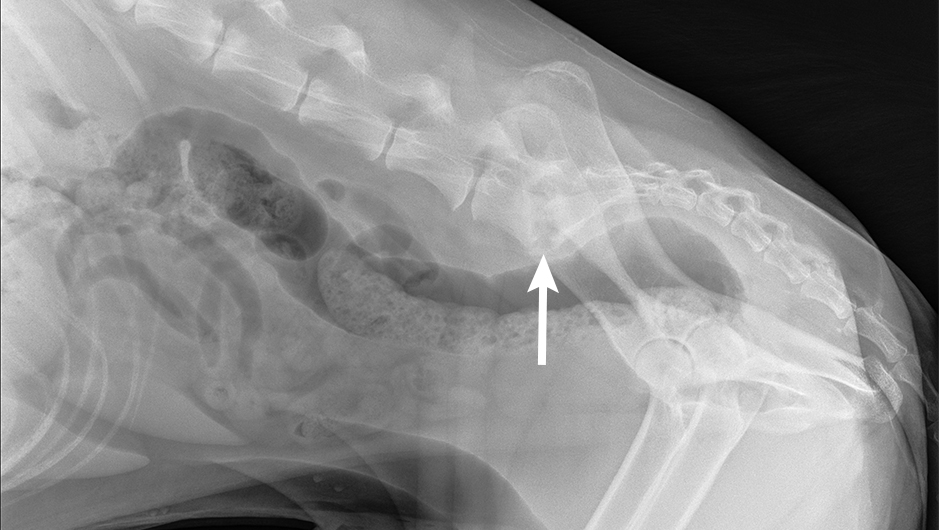

Discospondylitis Causing Back Pain in a Dog Clinician's Brief Epistaxis Dog Clinician's Brief In 56 dogs, epistaxis was found to be secondary to a systemic disease: Following are differential diagnoses, listed in order of likeliness, for patients presented with epistaxis. Epistaxis is one of the most dramatic presenting complaints in small animal medicine. Here are some tips to get the. So, you are at home with your pet and a bloody nose starts. Epistaxis Dog Clinician's Brief.